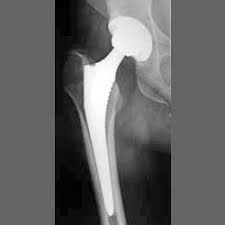

De

revalidatie na een operatieve heelkundige of orthopedische ingreep ( zoals knieprotheses,

heupprotheses, schouderprotheses of na een fractuur) wordt frequent gedaan in

onze praktijk.